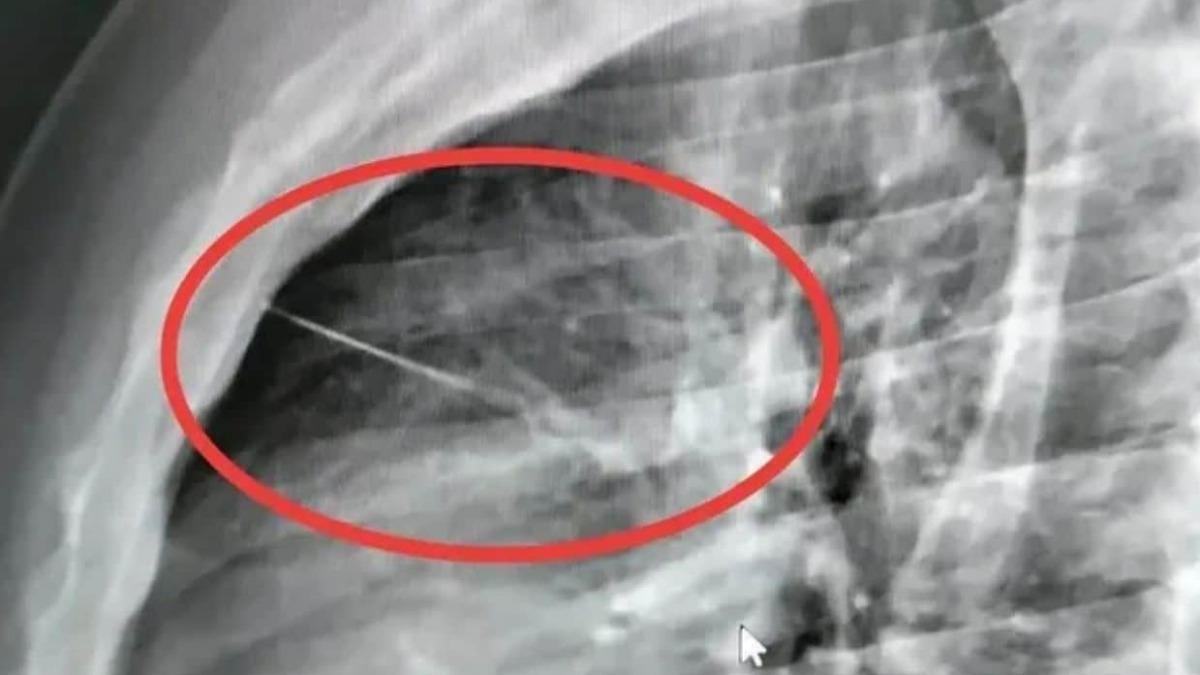

一名泰國武里南府男子布恩勒特·薩塔拉姆(Boonlert Sattaram)因胸口疼痛就醫,醫師發現其胸腔內有一根長達七公分的針幾乎刺穿心臟,導致他目前情況危急。事件發生於Krasang區,起因於布恩勒特回家後躺下休息時疑似被針刺傷,經救護人員送醫後,醫師透過X光檢查確認異物。其家屬索豐(Sophon Nokprom)懷疑該針為縫衣時遺留,手術難度高且風險大,目前尚未公布手術後狀況。